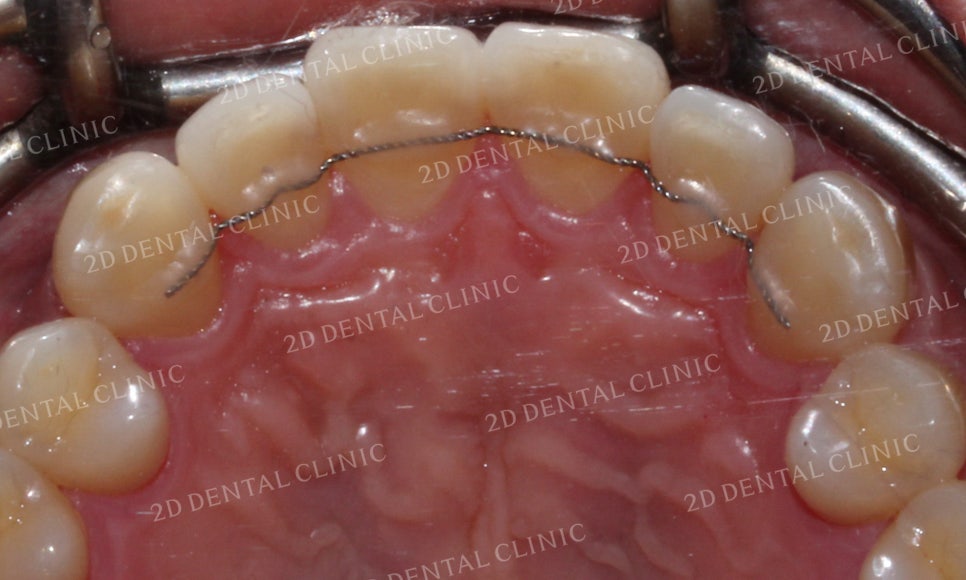

상악의 설측면 사진입니다.

표시된 부분의 21번 치아가

유독 회전이 심한 모습이었는데요

이로 인해 측절치가 중절치의

뒤쪽으로 파고들면서

치간에 치석과 플라그가 쌓이고 있는 상태였습니다.

그러나 교정 후 치아가 겹쳐진 부분들이 사라지고

삐뚤거리던 크라우딩도 사라지면서

가지런해진 치아들을 볼 수 있습니다.